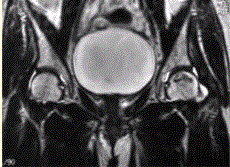

问题 患者男,47岁,左髋部疼痛及压痛6个月,“4”字试验阳性。左髋关节内、外旋活动受限。检查提示:左髋关节活动轻度受限,大腿上部轻压痛。血常规检查正常。髋关节CT及MRI如下图。 股骨头缺血性坏死早期诊断的最佳影像学检查方法是

选项 A.CT B.MRI C.X线平片 D.ECT E.USG F.PETCT

答案 B